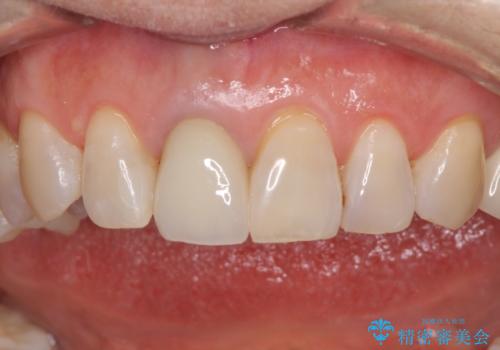

金属を全てセラミックに メタルフリー治療

上下奥歯の抜歯を同時期に行わず、下顎の治療を終えてから上顎を抜歯して治療を進めたため、1年ほどの期間を要しました。

口の中を一切気にしなくて良くなり、患者様には大変満足していただきました。